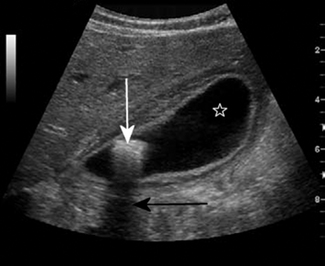

Reflection is a very important property of sound waves, as it provides echoes at tissue boundaries, and these are used to depict structures in diagnostic ultrasound. It also gives some information about the nature of tissues. A cyst, which mostly contains fluid, will return few or no echoes (the signal is termed hypoechoic or anechoic) from within itself, as shown in Figure 42.1, while a haemorrhage will return echoes from within itself (the signal is echoic or hyperechoic), as shown in Figure 42.2. This is because a haemorrhage also contains blood cells and proteins (which return echoes) in addition to just fluid. The walls of a cyst may return strong echoes at the capsule–fluid boundary.

Figure 42.1 The cysts within this polycystic ovary contain watery fluid and appear anechoic (echo free).